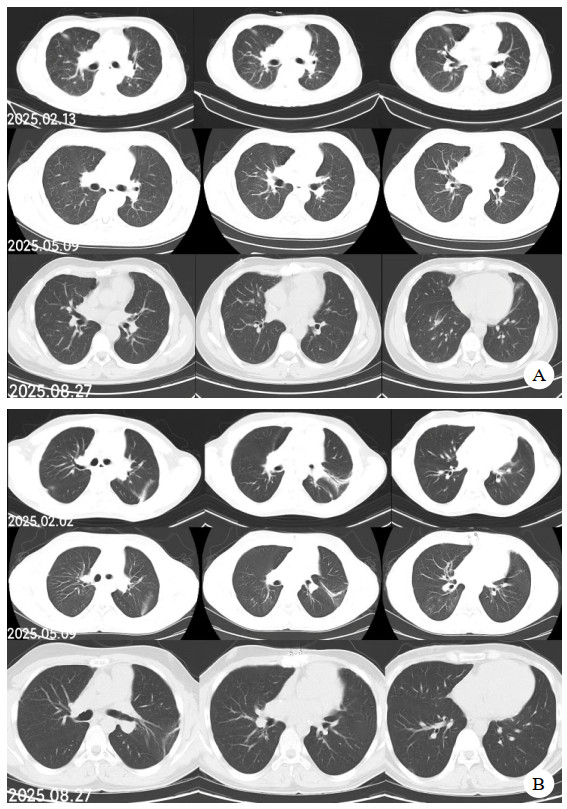

同时给予镇痛、镇静联合肌松,去甲肾上腺素泵入维持血压,俯卧位通气,B某入院后出现高热,经验性给予美罗培南联合万古霉素抗感染治疗,后降阶梯调整为哌拉西林他唑巴坦联合万古霉素治疗;C某抗感染方案为经验性使用万古霉素联合哌拉西林他唑巴坦治疗,痰培养出鲍曼不动杆菌后改为替加环素、头孢哌酮舒巴坦及万古霉素治疗;根据《刺激性气体中毒诊治专家共识》[5]中关于重症患者的治疗措施,同时给予2人泮托拉唑抑酸护胃,氨溴索、富露施化痰、甲泼尼龙抗炎、西维来司他纳及乌司他丁清除炎性介质,维生素C抗氧化、保肝、输血补液,纤支镜吸痰及肺泡灌洗,维持水电解质平衡及营养支持治疗,特别考虑到肺损伤情况,在使用有创通气时给予超保护性通气策略[5, 7];2人仍先后出现气胸、纵膈气肿,行胸腔闭式引流;持续V-V ECMO治疗15 d后,肺部纤维化不可逆转,高分辨率CT肺纤维化评分 > 75%(图 3、4),符合终末期肺病标准,有肺移植指征[8],经评估后2人顺利完成病变肺组织切除(图 5),双侧序贯肺移植,术后患者复查胸片肺部恢复正常(图 6),2位患者术后气管切管接呼吸机辅助通气,并给予泼尼松、他克莫司、吗替麦考酚酯抗排异治疗,其余根据病情给予万古霉素调节肠道菌群、抗感染、保肝、抗凝、呼吸康复锻炼等治疗,后顺利脱机、拔除气切套管,病情稳定出院,后续规律复查胸部CT(图 7)恢复良好。

| 注:图A为B某;图B为C某 图 7 肺移植术后第2个月、5个月、8个月CT影像 |